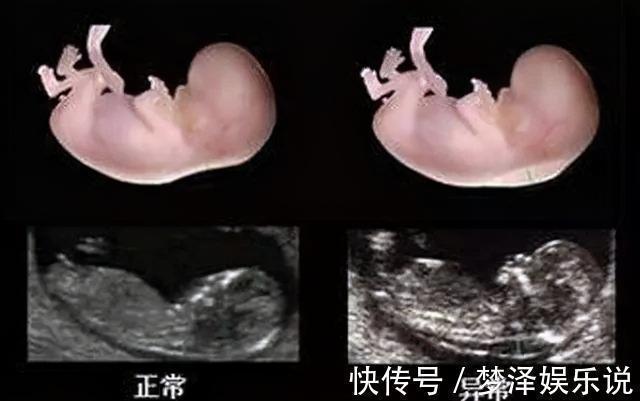

预防“唐氏综合征”,这两项检查很关键?第一项检查:NT检查指的是检查胎儿的“颈项透明层”,看胎儿颈椎的厚度,并参考临床标准,来确定胎儿存在唐氏综合征的风险。因此,这项检查又被称为“早唐筛查”。【检查时间】:怀孕11-14周是最好的检查时间,一般在孕12周产检时一起做。【检查方式】:B超检查,不需要憋尿。